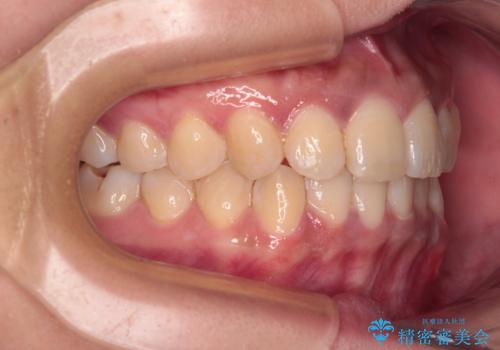

前歯のデコボコと隠れてしまう下顎前歯 インビザラインですっきりと改善

- 前歯のデコボコと、深い咬み合わせにより前歯が隠れていることを気にして来院された患者様です。

海外に長期滞在する予定があるとのことで、インビザラインにて矯正治療を行うこととしました。

インビザライン発注後に長期滞在先から2年間ほど帰国することができず、インビザラインの有効期限内に終了できるのか不安でしたが、矯正治療開始後は十分な装着時間を達成され、1年未満の期間で無事に終えることができました。